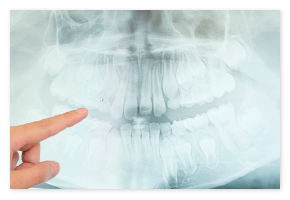

- レントゲン写真・歯型

顎の骨や歯の形のバランス等を診断します。